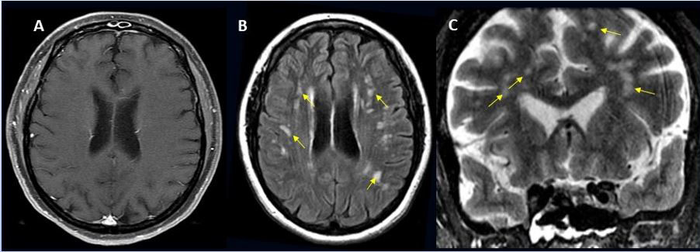

The most common brain complications were: strokes and brain bleeding, followed by brain inflammation, sinus venous thrombosis, acute demyelinating encephalomyelitis, posterior reversible encephalopathy syndrome, and vasculitis.

Study Results

Image Credit: Radiological Society of North America and Scott H. Faro, M.D.